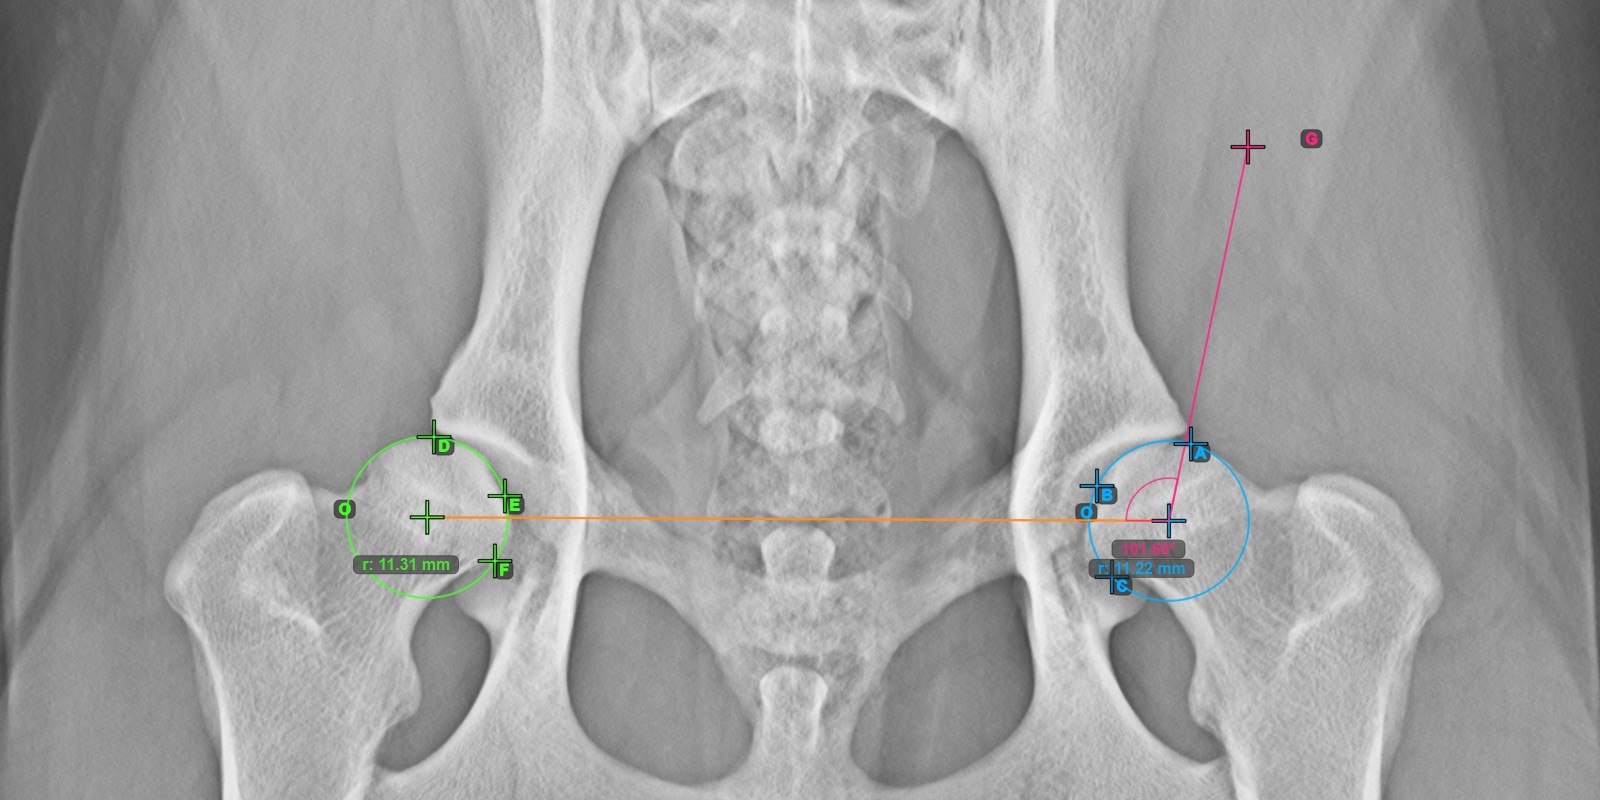

Calculate the right Norberg Angle measurement by marking a line on the effective edge of the right Acetabularis bone, completing the entire advanced measurement.

Mark a point near the right Caput Femoris and drag it along the effective edge of the right Acetabularis bone, forming the terminal side of the right Norberg Angle.

The drawn line must be a tangent to the effective edge of the right Acetabularis bone. The value and arc of the angle is automatically calculated.

The image below depicts the typical placement of the line and the calculated Norberg Angle measurement.